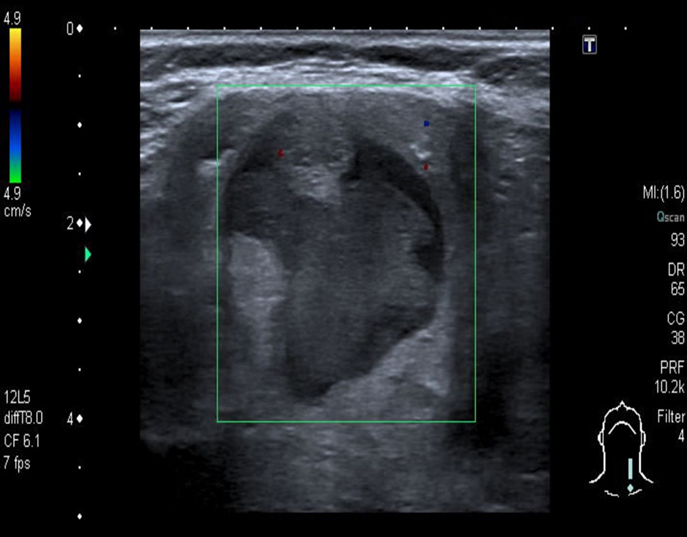

B-Mixed echogenicity thyroid nodule

Ultrasound thyroid (left lobe; longitudinal plane)

A rounded mixed-echogenicity nodule with irregular (lobulated) margins contains hypoechoic and hyperechoic components.